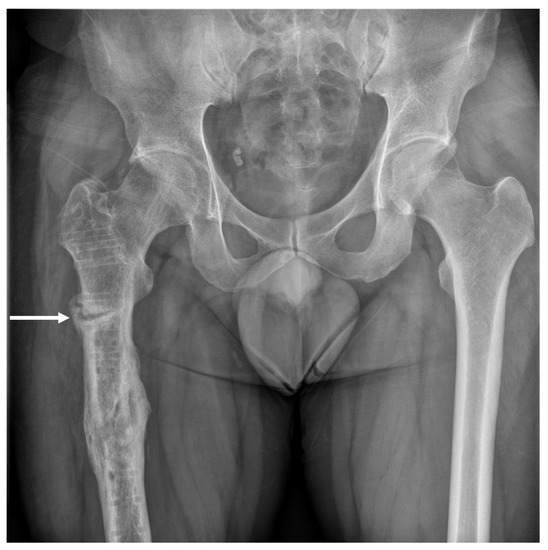

Subtrochanteric Insufficiency Fracture Occurring 5 Years after Surgery at the Steinmann Pin Insertion Site for Fracture Reduction